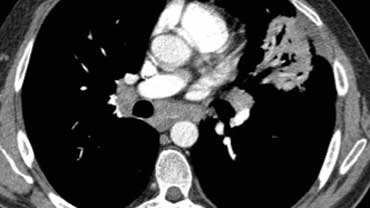

Bệnh nhân với Ung thư hạch bạch huyết lan tỏa.

Lưu ý phân bố khu trú của tổn thương.

Đặc điểm này có giá trị trong việc phân biệt Ung thư hạch bạch huyết lan tỏa với các nguyên nhân khác gây dày vách liên tiểu thùy như phù phổi hoặc sarcoidosis.

Ngoài ra còn có hình ảnh hạch to.

Bệnh nhân khác với Ung thư hạch bạch huyết lan tỏa có dày vách liên tiểu thùy (mũi tên vàng).

Kèm theo tràn dịch màng phổi (mũi tên xanh) và tổn thương di căn phổi (vòng tròn).